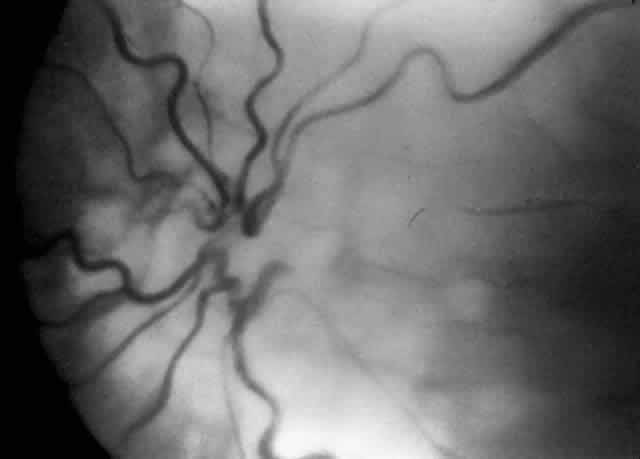

Fig. 3. Dilated and tortuous vessels in the posterior pole, which by definition is plus disease.